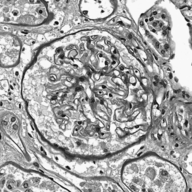

Image datasets in digital pathology applications often consist of consecutive slides stained differently, each staining providing specific information on the same region of interest (see Figure 1, first row). Even though differently stained slides appear very different, there is often a significant amount of consistent information between them. For example, they may both share the same counterstain (e.g. haematoxylin), or they may highlight different parts of the same structure.

The analysis and integration of information from different stainings is usually performed with reference to a specific organ, structure, or pattern observed in the tissue. For example, to diagnose pathologies such as breast cancer or kidney allograft rejection it is necessary to study the inflammatory micro-environment of the organ. In these cases, the relevant information is the distribution of immune cells (e.g. macrophages or lymphocytes) in relation to important structures of the organ, such as glomeruli for the kidney, or lobules for the breast.

Objects to be segmented, e.g. glomeruli, are generally easily identified between stainings as globally they exhibit the same structure and texture, see Figure 1. It should therefore be possible to bias the network to learn stain invariant features. This work investigates this possibility by modifying the data presented to the network in an unsupervised manner. Borrowing domain adaptation terminology, herein the staining used for training and validation is referred to as as the source staining (irrespective of any transformations), and the stainings to which the network are applied as target stainings.

N.B. the intention is to present plausible colour profiles to the network. This does not necessarily correspond to biologically relevant image information but is explored for any potential for the tested staining modalities. Potential limitations are addressed, e.g. in Figure 1 the bright red colour (chromogenic reaction used to detect CD34, a marker of blood vessel inner lining) could be successfully transferred but it is not localised as in the original image.

Next is a strategy to extract biological information that is consistent across different stainings—the haematoxylin counterstain. Despite this biological plausibility, it does not result in good results. Indeed, the haematoxylin transformed images vary greatly between the different stainings (see Figure 1, second row). Several factors may explain this: 1) haematoxylin’s concentration relative to the primary stain may vary from one staining to another, resulting in different shades of blue and fixation amount; 2) as a counterstain, haematoxylin may become mixed with another stain in structures that are targeted by both. These result in a color mixing that is in practice not perfectly unmixed by a color deconvolution algorithm.